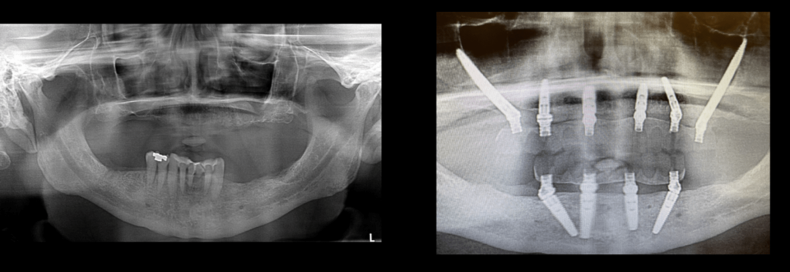

Case #1:

One Zygomatic Implant per side, 4 additional implants in upper jaw

All-on-4 on lower jaw